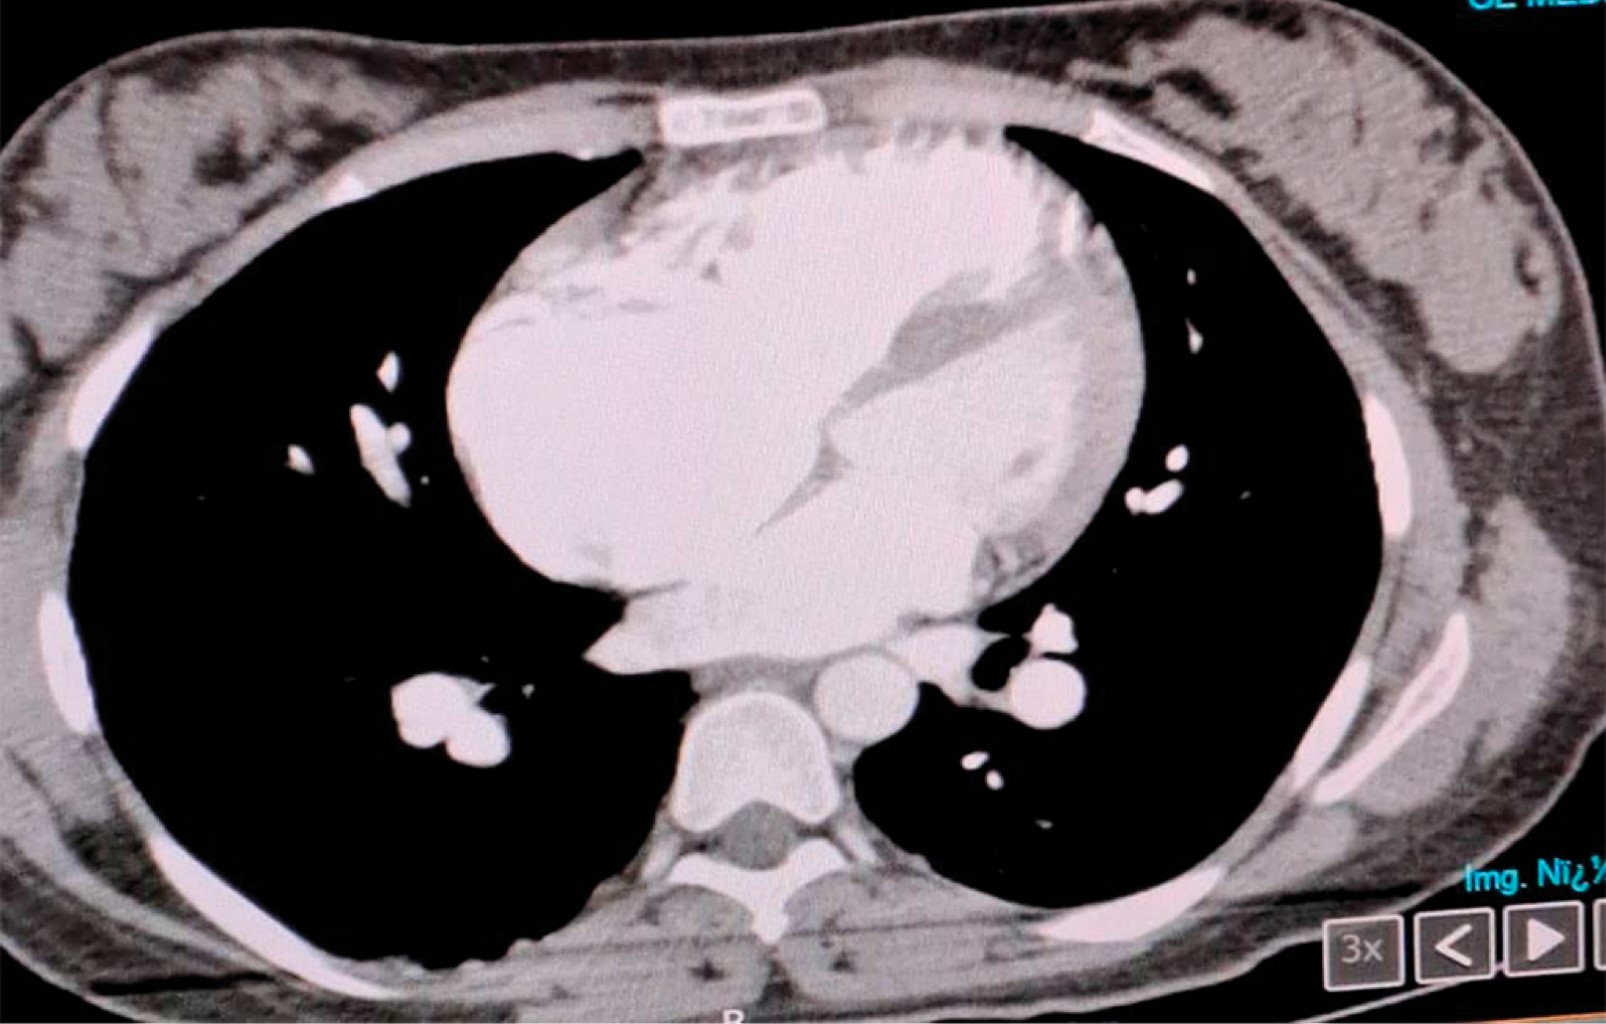

Eisenmenger syndrome in an obstetric patient. Case report in the Intensive Care Unit

Introduction: Eisenmenger syndrome (SE) is caused by elevated pulmonary vascular resistance. Pulmonary hypertension is due to stimuli that cause endothelial dysfunction, such as sustained hypoxia, friction stress, venocapillary hypertension, and other noxious stimuli. In pregnant women with ES, the prognosis is worse, due to the hemodynamic changes typical of pregnancy. Clinical case: the case of a pregnant patient with Eisenmenger syndrome is described, who is admitted to the Intensive Care Unit, where it is diagnosed and managed, showing a torpid evolution. This is one of the few cases of ES in obstetric patients reported in Mexico. Conclusion: ES is a medical condition that has been seen to affect the quality of life of patients. Maternal mortality associated with SE and in recent decades despite new treatments has not benefited. Pregnancy remains an absolute contraindication.

Figure 1

Figure 2

Figure 3

Figure 4